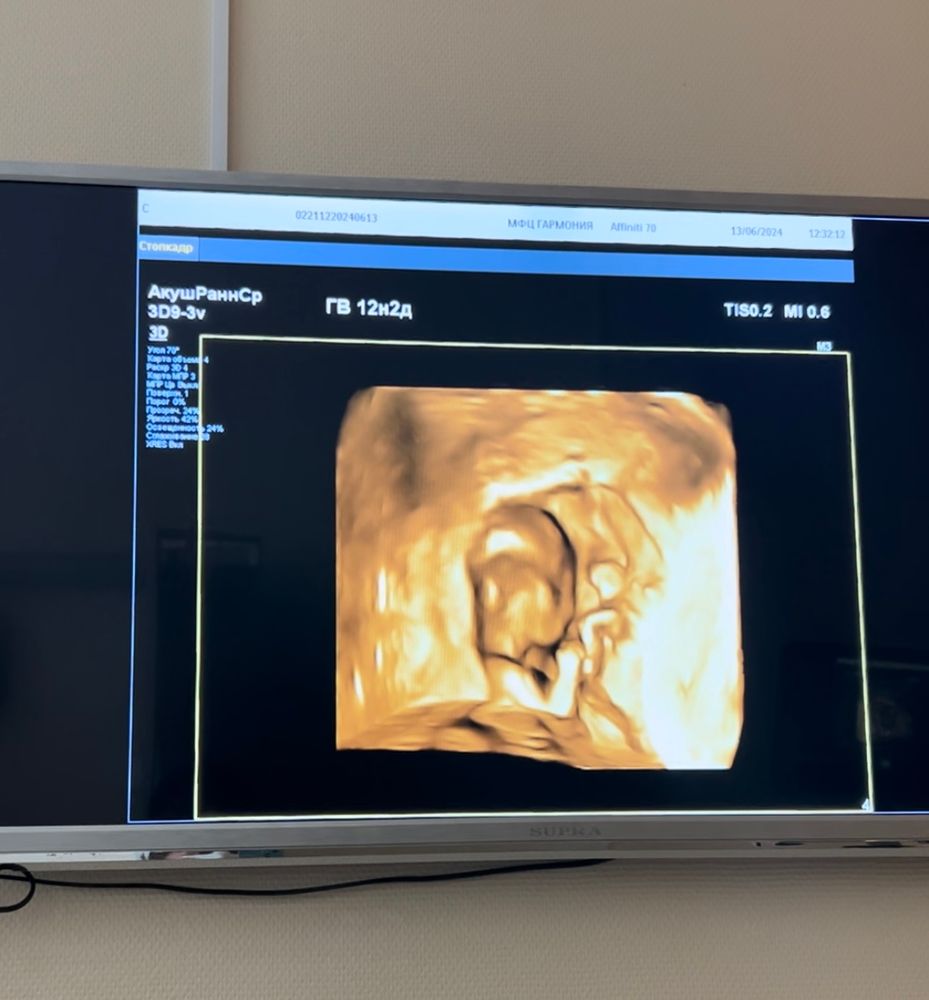

Пол малыша

На этом сроке смотрят ТОЛЬКО в профиль. Снизу недель до 14 там все одинаковое. Непонятно, что вы там увидели...

Blue Berry, к тому же малыш рос в тот момент не по своему сроку,срок был больше 12,2)

Blue Berry, если вы начитались в интернете что пол невозможно рассмотреть на таком сроке-то это только ваше дело и мнение. У детей начинает формироваться все с 10 неделе ,если не раньше. У мальчиков чаще всего быстрее. К тому же ,предварительный пол говорят многим,и в каких то случаях он становится действительным.

Бугорок к верху - думаю,что мальчик.

Насколько я знаю, именно в 12 недель смотрят по половому бугорку в профиль. Между ножек рановато. Но предположу девочку